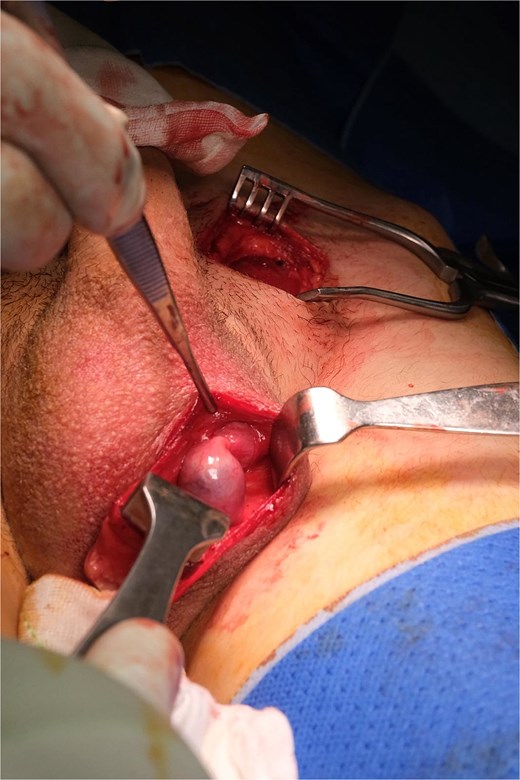

An elongated gubernaculum tethered high in the scrotum was also noted (Fig. 4). Following careful dissection, the testis was freed, revealing a viable appearance and adequate cord length for scrotal mobilization (Fig. 5). A subdartos pouch was created via a left paramedian scrotal incision, and the testis was delivered into the scrotum via a tunnel created by gentle blunt dissection (Fig. 6). The testis was fixated in three-points with a 4-0 polydioxanone suture. The contralateral hemiscrotum was also explored utilizing the same incision, where the right testis was found to have a normal lie and attachments. It was likewise fixated.

Completely mobilized left testis, showing viable appearance and adequate cord length for tension-free mobilization.

Creation of subdartos pouch in the left hemiscrotum prior to testicular fixation.